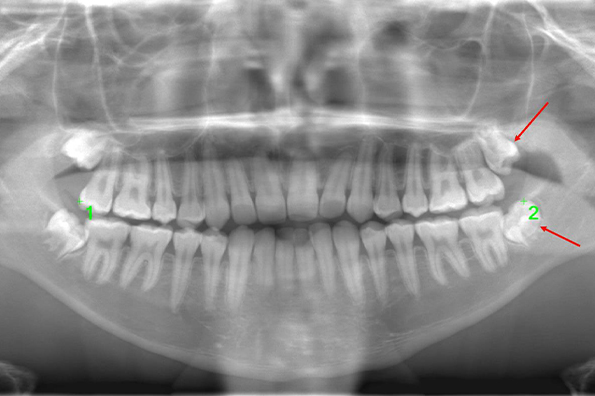

CASE 2

| 主訴 | 左上下親知らず抜きたい |

| 抜歯期間 | 30分 |

| 抜歯費用 | 約2,500円(保険内) 別途CT撮影で3,000円 |

| 抜歯内容 | 左上下の親知らず抜歯 |